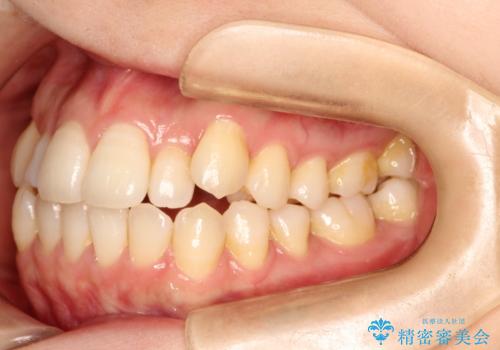

インビザラインで八重歯の矯正

- 八重歯を治したいとのことで、来院されました。

インビザラインにて、上顎の歯と歯の間をわずかに削り、並べる計画としました。

使用時間を守っていただけたので、比較的スムーズに矯正を終了することができました。